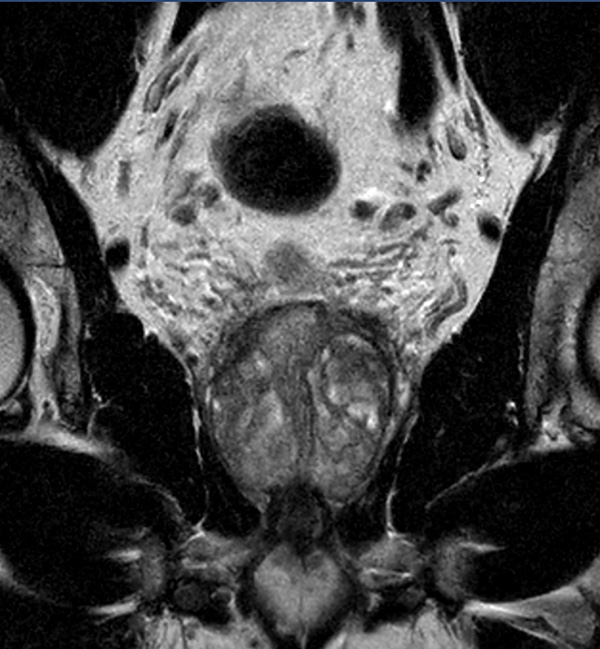

A 60-year-old male with elevated PSA and weak urinary stream underwent MRI. The exam includes high resolution DWI and ADC mapping as well as dynamic imaging. The prostate gland measures 5.2 x 4.4 x 5.9 cm in maximal transverse, AP, and craniocaudal dimensions, respectively, corresponding to an approximate glandular volume of 70 ml. Heterogeneous nodular hypertrophy is seen along the central transitional zone, with hypointense pseudo capsule, indicative of BPH, without dominant T2-hypointense nodules. Patchy T2-hypointense foci are noted throughout the peripheral zone bilaterally at the base, mid-gland and apex, with total PI-RADS score 6, so probably benign. No dominant nodular areas of restricted diffusion are evident. A geographic T2-hyperintense focus in the peripheral zone at the right base to mid-gland, paramidline shows asymmetric restricted diffusion, total PI-RADS score 10. No dominant lesions, greater than 1 cm. Clinical correlation and follow-up are advised.